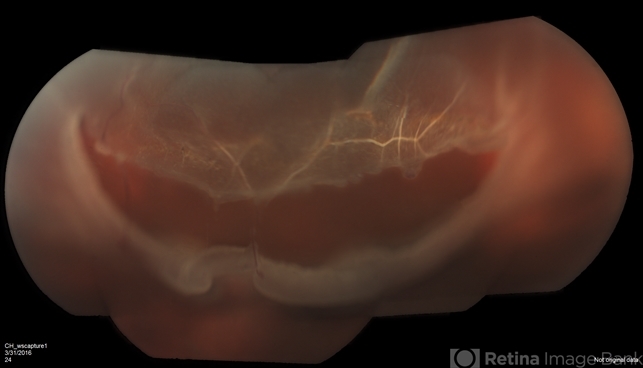

Excellent representation of this inferior retinal tear Nichole. A fine montage! Thank you.

- giant retinal tear, retinal tear

- Giant retinal tear montaged on Anterior Segment due to the Detachment being very bullous.